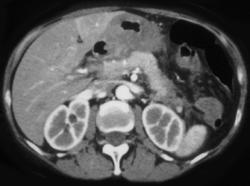

Gastric Adenocarcinoma